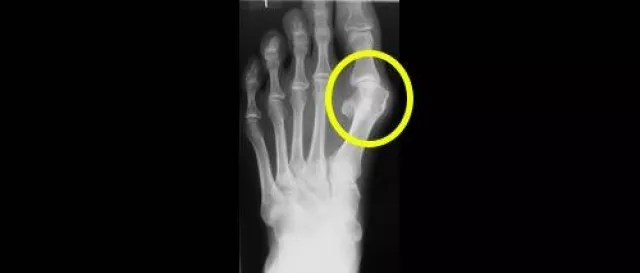

Als medizinische Besonderheit führt die ENDO-Klinik bei periprothetischen Gelenkinfektionen den einzeitigen Wechsel durch. Schätzungsweise sind weit mehr als 6.000 bis 7.000 Patienten jährlich in Deutschland betroffen, weil sich nach einer Operation Bakterien auf dem Gelenk ausbreiten. Spätinfektionen können sogar noch acht Jahre nach der Operation auftreten. Eine akute Sepsis ist sogar lebensbedrohlich. Im Gegensatz zu anderen Kliniken wird in Hamburg in einem Guss die Infektion behandelt und ein neues Gelenk eingesetzt. Der Vorteil: Der Patient muss nur einmal ins Krankenhaus, muss nur einmal narkotisiert werden, die Erfolgsraten sind sehr gut und die Krankenkassen rechnen dabei nur einmal ab.